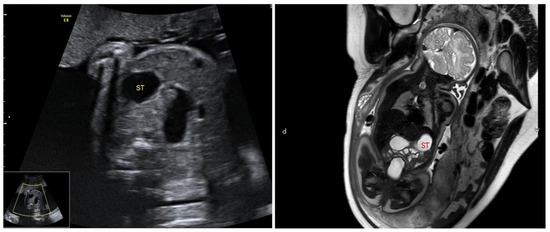

Based on fetal ultrasound and MRI assessments, lower digestive tract dilatation was observed in 72 fetuses. In these cases, dilated bowel appeared separately, with no connection with gastric bubble, indicating that the dilatated segment was in the jejunoileum or colon (Figure 2). The average GA at first time of diagnosis was 31.4 ± 5.1 weeks of gestation (range, 19+5–40+6 weeks).

Figure 2. Bowel dilation in ultrasound and MRI examination.